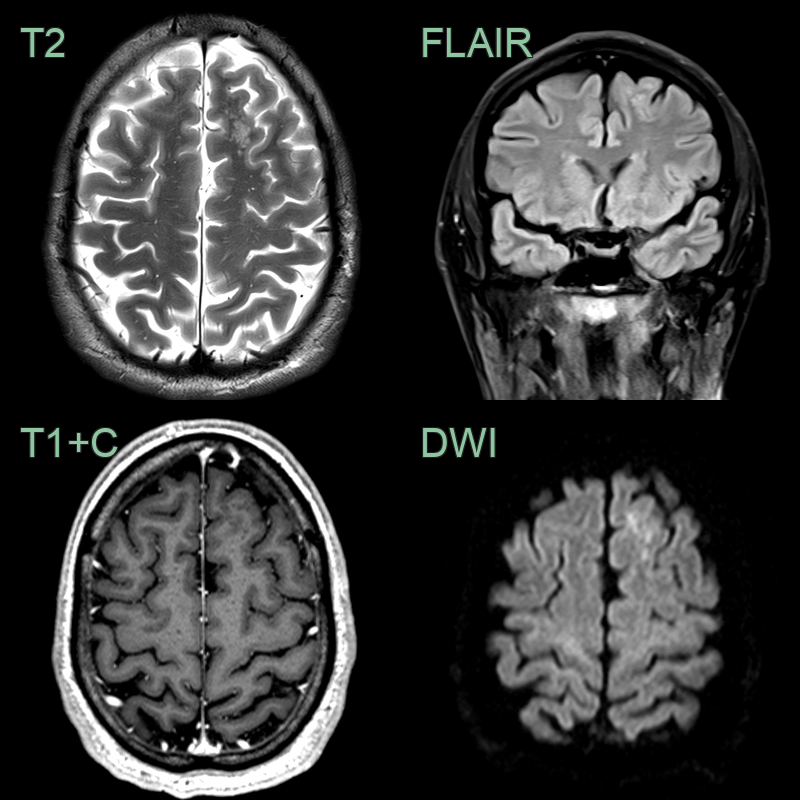

• The "soap bubble" T2-hyperintense lesion in the left cerebral hemisphere without mass effect, diffusion restriction or enhancemetn was typical of MVNT.